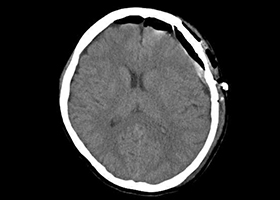

[術後画像検査]

-

術前MRA -

術後MRA

術後はバイパス血管が脳内に向かって出現しています(赤丸印)。

術後脳血流検査(SPECT)

術前 術後

術前血行不良であった領域(オレンジ部)が術後には血流改善(緑色)している。患者様の症状は消失し、社会復帰されました。